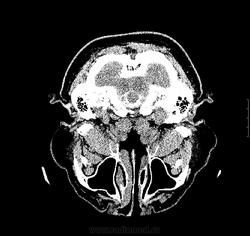

3.06.12 больному выполнена КТ без контраста, заподозрено подкравливание из аневризмы бифуркации базилярной артерии, либо ее тромбирование. Рекомендовано проведение СКТ-АГ.

04.06.2012 проведено СКТ-АГ, выявлено объемное образование ската, спинки турецкого седла с супраселлярным  ростом. Небольшое неоднородное накопление контраста в строме опухоли.

Я извиняюсь-может быть, не в тему,но мне интересно  на представленных сканах МР(КТ) признаки внутричерепной гипертензии найти.Просто недавно  разбирали эту тему, поэтому сейчас обращаю  внимание на все,включая форму глазных яблок и состояние зрительных нервов, не говоря уже про узость боковых желудочков ( здесь кроме незаращения лисков прозрачной перегородки, желудочки в норме).Согласна с Евгением по поводу признаков наличия крови ( недавно случай выставлялся,кажется, Евгением Широковым).

Helios, КТ было выполнено до имплантации люмбального дренажа. Пациент клинически "заболел" гипертензией совсем недавно. Не думаю, что можно найти принаки ВЧГ.